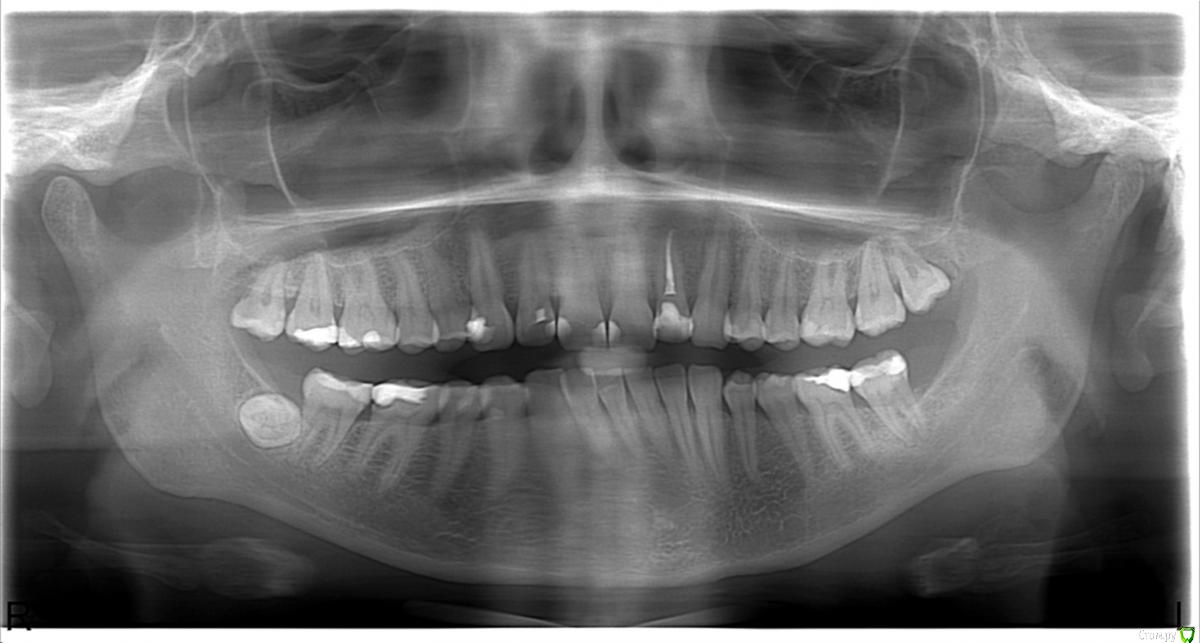

Уважаемые стоматологи! Сейчас нахожусь в процессе лечения 6 зуба на нижней челюсти ( на фото слева). Врач депульпировал, поставил временную пломбу и через две недели поставит постоянную. Но врач меня предупредила, что на зуб надо будет делать вкладку с коронкой, так как пломба большая.

Может к снимку нужна фотография пломбы и зуба на фотоаппарат?post-24898-0-30249500-1440432711_thumb.jpg

Я так понимаю снимок сделан до лечения?если есть возможность,выложите хотя бы прицельный Rg снимок и фото самого зуба,так можно будет более объективно и информативно ответить на ваш вопрос..